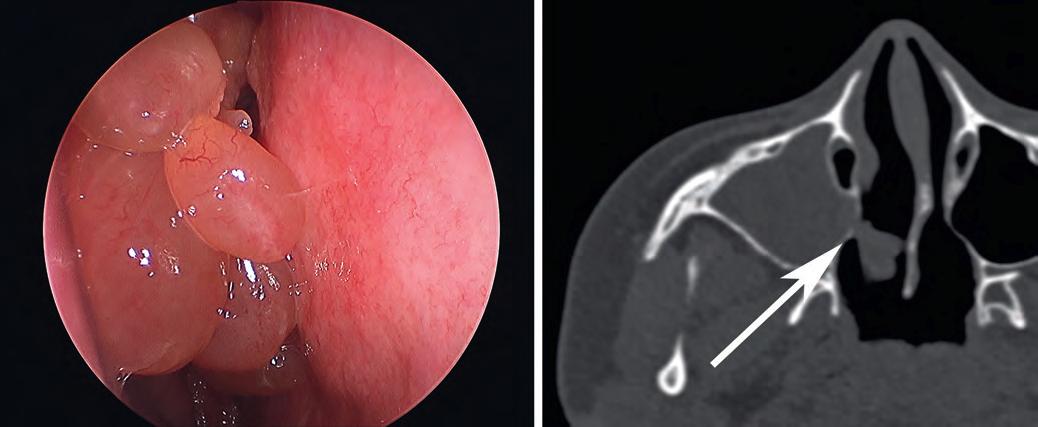

The typical clinical appearance of inflammatory polyps is that of bilateral, multiple mucoid polypoid masses with a translucent appearance involving the nasal cavity (A). The antrochoanal polyp is a subtype of inflammatory polyp arising from the maxillary antrum and protruding into the nasal cavity via a stalk (arrow) through the nasal choana (B). (A, Courtesy of Dr. Douglas Reh.)

asthma, aspirin intolerance, cystic fibrosis, diabetes mellitus, and other conditions. Inflammatory polyps are typically seen in adults (except for cystic fibrosis-associated polyps), with no sex predilection. They involve the nasal cavity (especially the lateral wall) and maxillary and ethmoid sinuses and are usually bilateral (Fig. 1.4A). In addition to the symptoms of the underlying condition (e.g., allergies), sinonasal inflammatory polyps may cause nasal obstruction and pain. A subtype of inflammatory polyp known as antrochoanal polyp arises from the maxillary antrum and extends through the sinus ostia into the nasal cavity, nasopharynx, or oral cavity (see Fig. 1.4B). Antrochoanal

polyps are usually seen in younger patients (teenagers and young adults), usually males, and are typically unilateral.

Inflammatory polyps are typically translucent and mucoid in appearance (see Fig. 1.4A). Antrochoanal polyps tend to be elongated with a stalk and fibrotic.